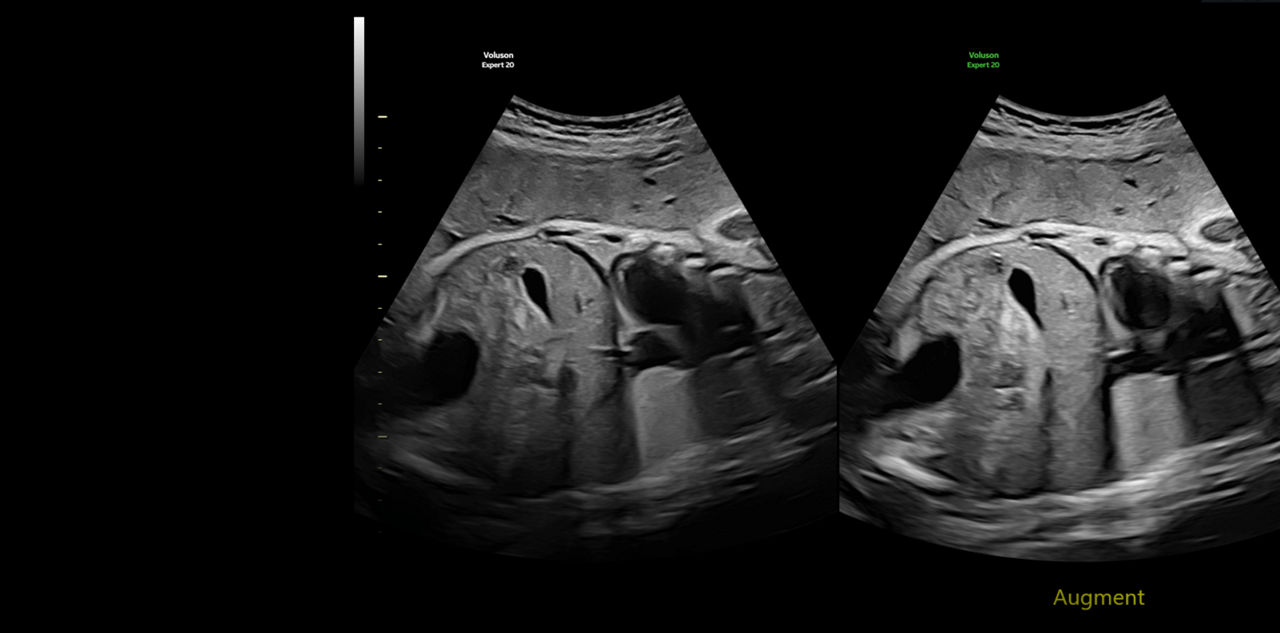

Refine Clinical Insights

Extraordinary clarity and definition so you can focus on early detection and intervention.

Accelerate Efficiency

Save time, steps, and effort by leveraging AI, automation tools, and ergonomic design